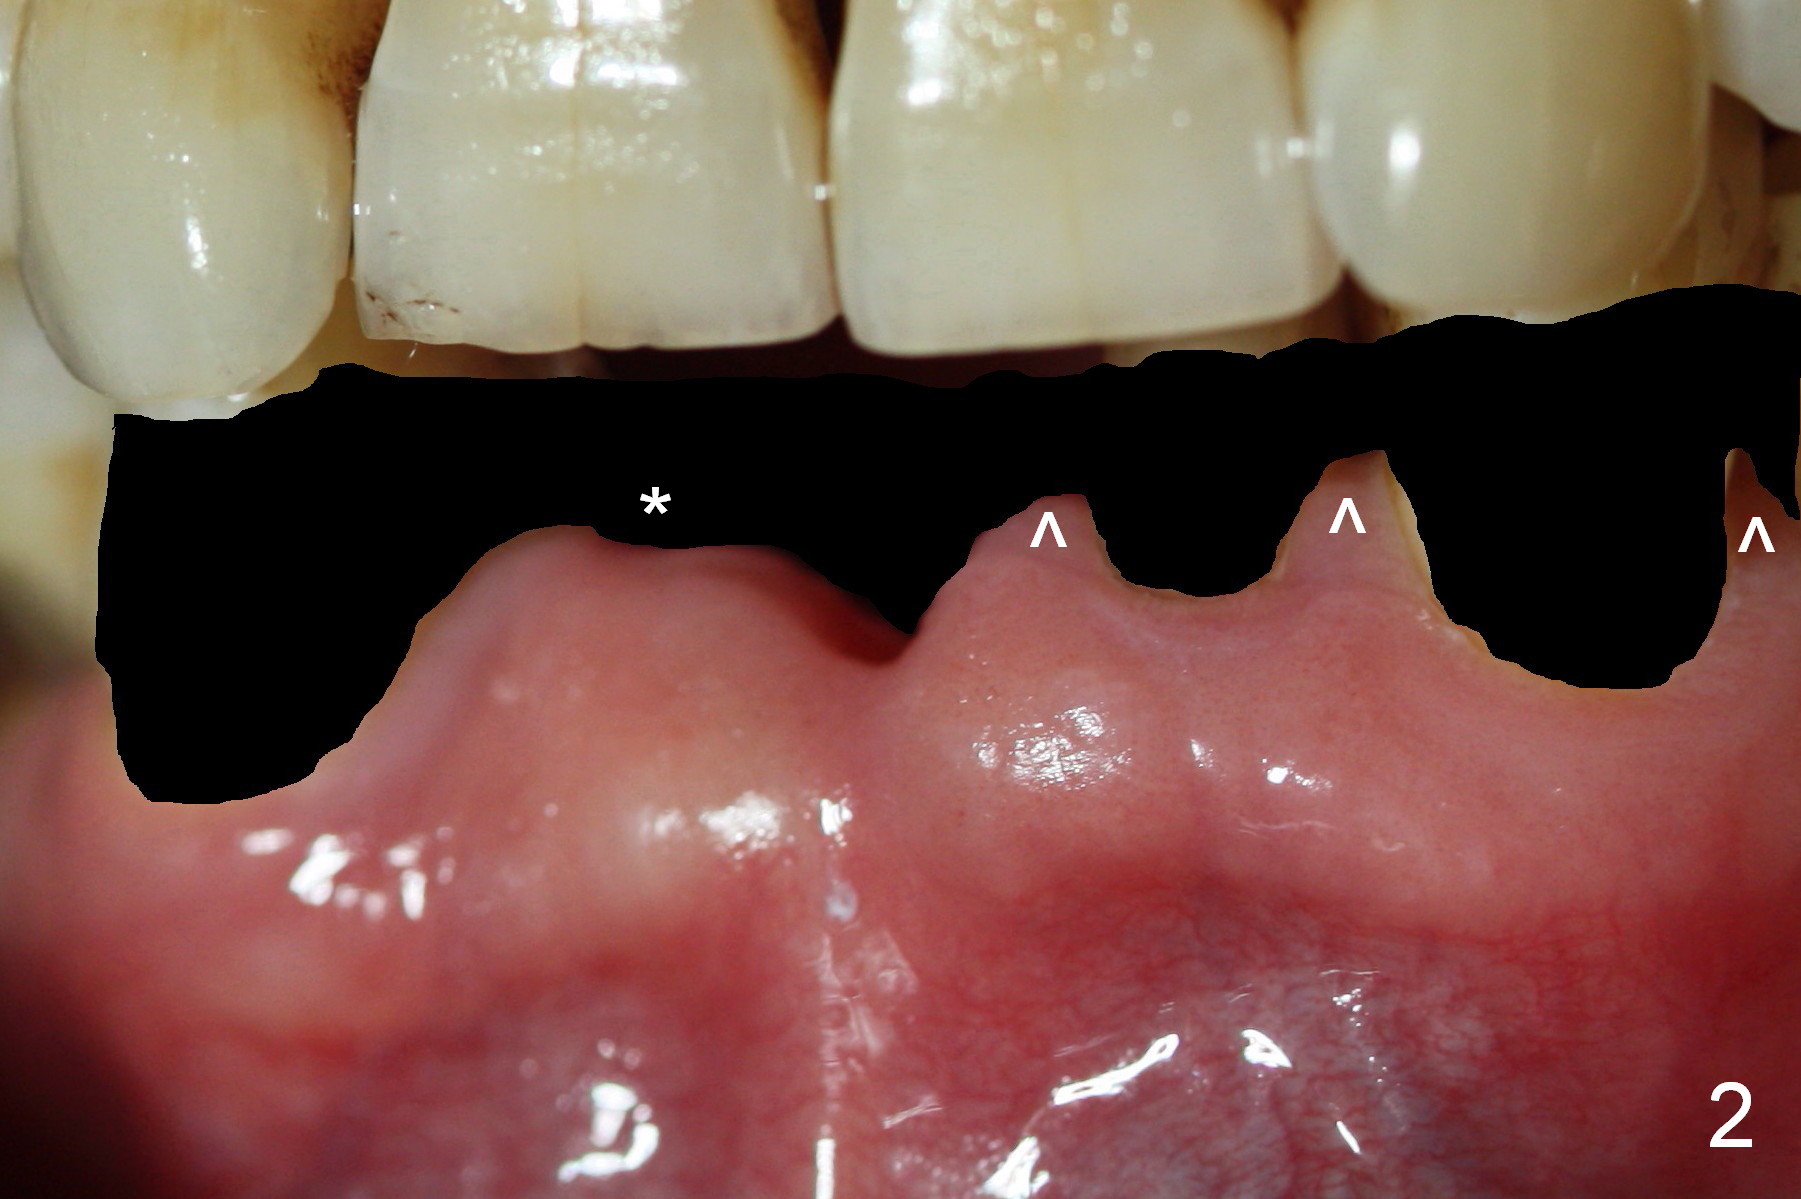

The teeth give the gingiva scallop shaped (Fig.1, 2). The scallop is less where the tooth is absent (Fig.2 *). The scallop must have been distinct when the tooth is just extracted with prominent papillae (Fig.2,3 ^).